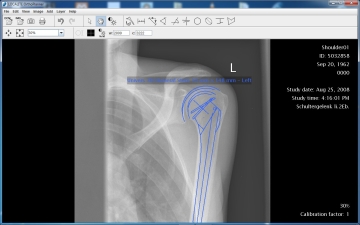

LOCALITE OrthoPlanner® - Digitale Prothesenplanung

Der LOCALITE OrthoPlanner ist eine Planungssoftware für den Einbau von Endoprothesen, die auf digitalen Röntgenbildern basiert. Die Software bietet die Möglichkeit, Endoprothesenimplantate beliebiger Gelenke und aller Prothesenhersteller zu planen. Winkel, Abstände und Größen können exakt gemessen und das Planungsergebnis archiviert werden. Röntgenfilmausdrucke und durchsichtige Plastikschablonen werden daher überflüssig.